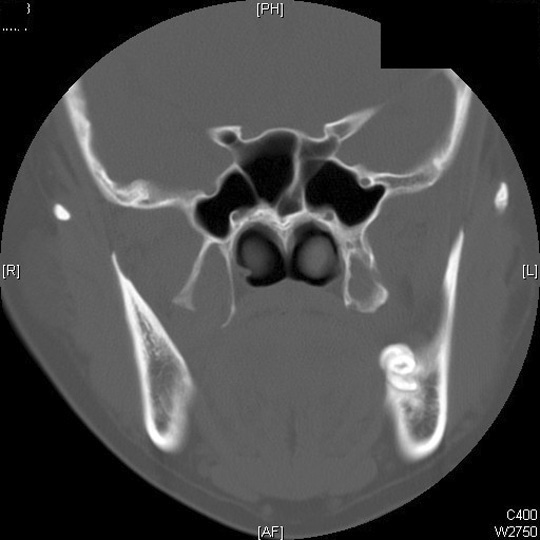

Identify the medial and lateral plate pterygoids. Click the image for labeling.